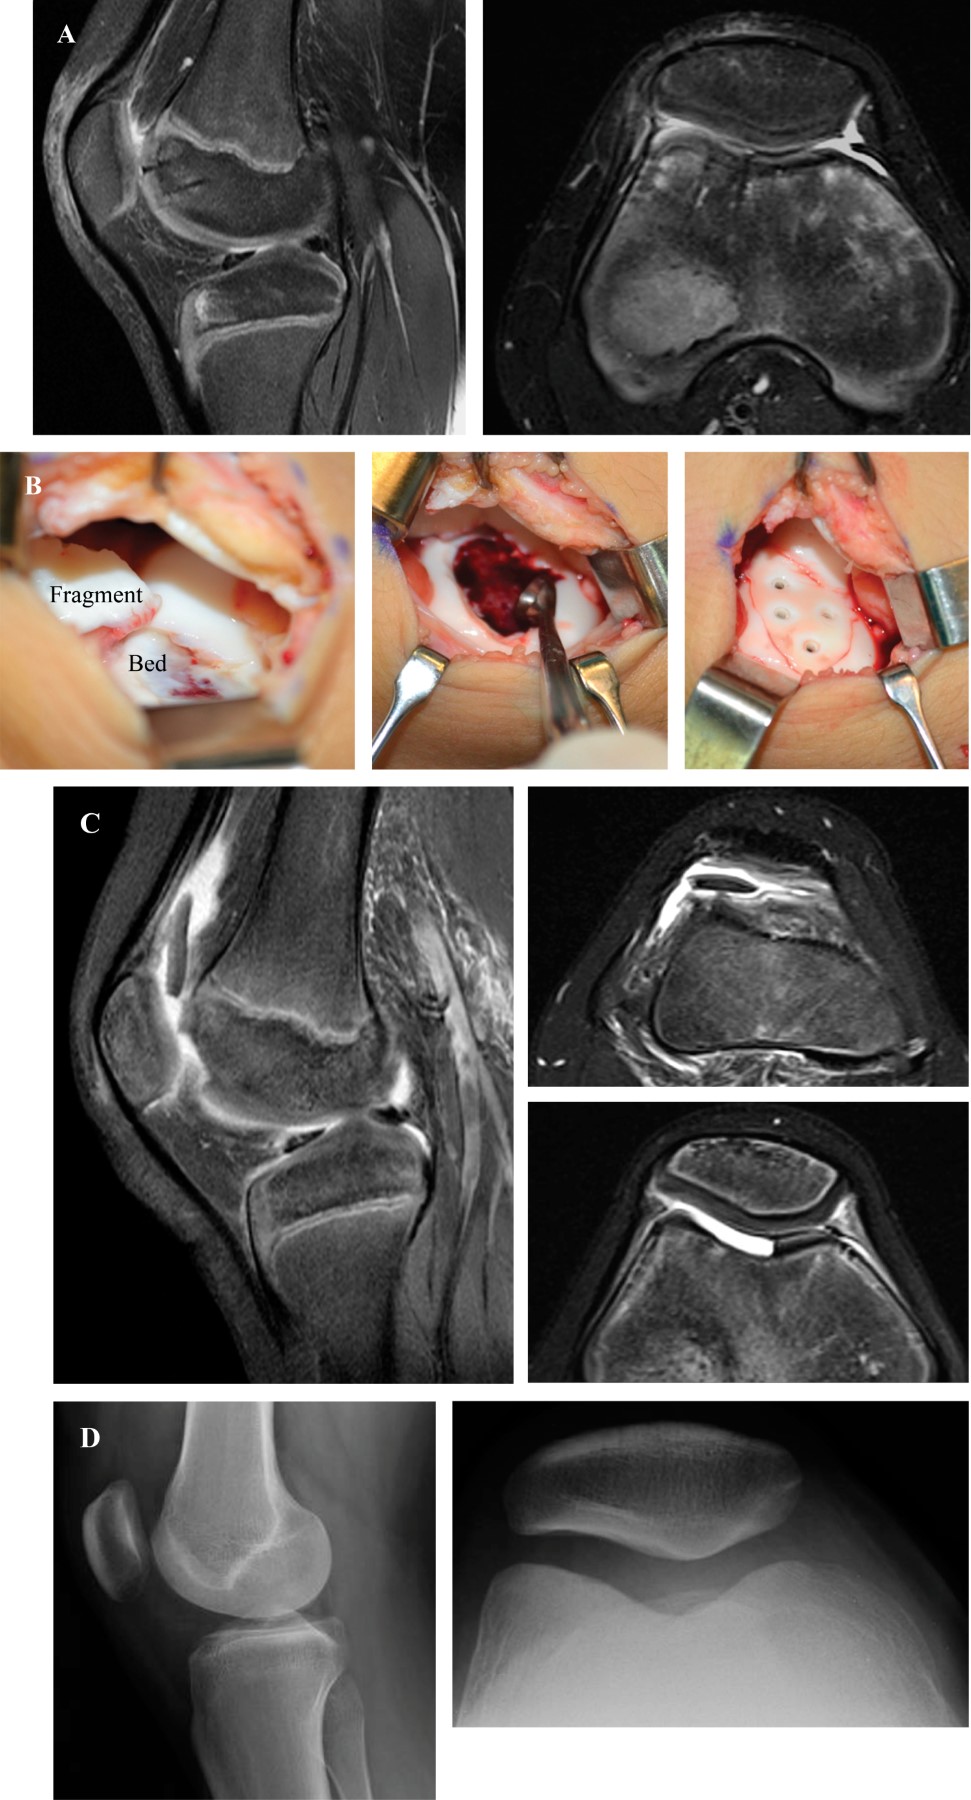

Osteochondral injuries in pediatric patients occur more often as a result of a direct blow on a flexed knee or shearing forces associated with an acute dislocation of the patella. The incidence of osteochondral fracture after patella dislocation was reported to be up to 39%.58 The patient with an OCF presents with a painful, swollen knee joint, reluctant to bear weight, and any attempt to flex or extend the knee if resisted. Tenderness over the injured portion of the articular surface may be found.

Plain radiographs with AP, lateral, merchant view, and 45o flexed tunnel view should be obtained. Traumatic osteochondral fractures are represented by a disruption of the subchondral line compromising the lateral femoral condyle, medial facet of the patella or both. The ability to visualize the fracture fragment on radiographs is dependent on the amount of subchondral bone the piece contains. Those with very small bone components are often difficult to detect. MRI is the gold standard study to determine the presence of an articular cartilage injury, although it can often underestimate the size of the cartilage lesion or osteochondral defect.59

Surgical treatment is preferred and depends on the size and location of the osteochondral injury. Arthroscopic removal of the fragment is indicated if the fragment is < 1 cm in diameter and is in a non-weight bearing articular surface (Figure 4). Reduction and fixation is the treatment of choice for larger osteochondral fragments where the cartilage is in good condition. Depending on the location of the lesion, this may be done either by open arthrotomy (usually for patellar lesions) or via arthroscopy. There are multiple fixation methods including metallic screws, bioabsorbable screws, bioabsorbable pins, autologous bone pegs, suture bridge, and fibrin glue (Hedgehog technique).60,61,62,63,64 Fixation of traumatic OCF may result in successful healing in adolescent patients regardless of the characteristics of the fragment (osteochondral versus chondral-only) and time elapsed since the injury (Figure 5). Fabricant et al.64 in a multicenter study evaluated 15 patients with a median age at surgery of 12.7 years. The injured sites were the patella (n = 6), trochlea (n = 5), and lateral femoral condyle (n = 4). The median fragment surface area was 492 mm2. Fixation with bioabsorbable implants was performed in all patients at a median of 1.6 weeks after the injury. One patient (7%) sustained a fall eight weeks postoperatively, requiring secondary surgery for excision of a dislodged fragment, and 1 patient (7%) underwent unrelated patellar stabilization surgery 3.4 years postoperatively, at which time the fragment was found to be stable. All 15 patients returned to sports and activities at a median time of around 6 months, with a median follow-up of 12 months. More recently, Kjennvold et al65 evaluated 10 patients (median age of 15 years) with a pure chondral fracture of the knee treated with internal fixation. The lesions were located on the patella (n = 7), the trochlea (n = 2), and the lateral femoral condyle (n = 1). Median lesion size was 250 mm2 (1.9-6.0 cm2). All patients were treated within two months of injury (4-58 days). All patients returned to preinjury level of sports and MRI showed retained fragments that integrated well with surrounding cartilage at follow-up. Mean Lysholm score at mean 5 years follow-up was 90 (73-100). Therefore, preservation of native articular surface cartilage should be considered the first line of treatment as long as the fragment does not have excessive fragmentation.

Osteochondral autograft transplantation surgery may be useful in the instance of an osteochondral injury that is not amenable to repair.60 Patellar stabilization is recommended if the osteochondral fracture is associated to an episode of patellar dislocation.66 Medial patellofemoral ligament (MPFL) reconstruction has shown better outcomes than repairing techniques.67 Complications after surgical treatment may include fixation failure, stiffness, quadriceps muscle atrophy, and post-traumatic arthritis. Patients with acute patellar dislocation can also experience recurrent subluxation or dislocation.